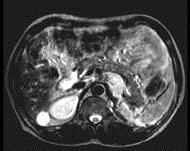

问题 女,34岁,无意中发现血压升高4 个月就诊,行CT检查,如图所示,下列说法正确的是 ( )

选项 A、考虑为左肾上腺嗜铬细胞瘤 B、考虑为左肾上腺转移瘤 C、增强扫描,该病灶周边明显强化,中心处强化不明显 D、考虑为左肾上腺腺瘤 E、CT示左侧肾上腺区可见一等密度块影,边界清楚

答案 ACE